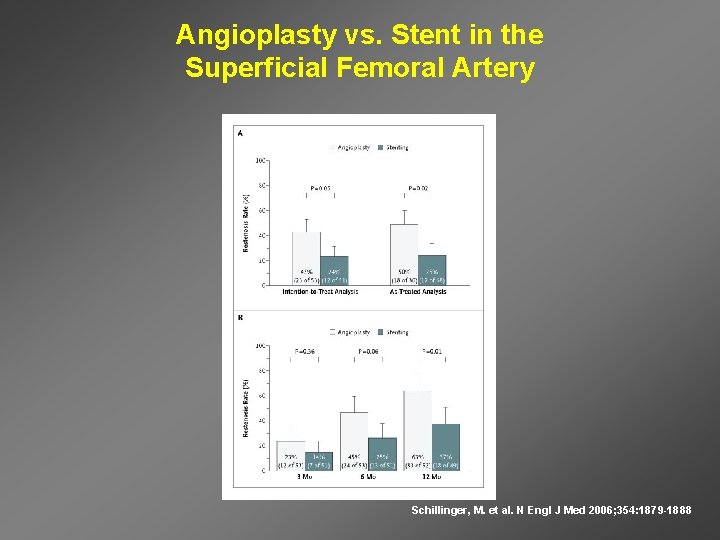

Angioplasty vs. Stent in the Superficial Femoral Artery Schillinger, M. et al. N Engl J Med 2006; 354: 1879 -1888

Clinical Effects of Primary Stenting vs Angioplasty for Femoral Dz Schillinger et al. N Engl J Med 2006; 354: 18791888.